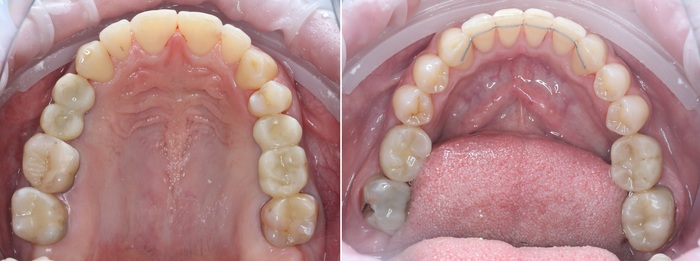

После установки имплантатов достаточно 3.5 месяцев до снятия слепков и изготовления временных коронок. Изготовление коронок проходило так же в два этапа по сторонам. Я не вижу смысла добавлять много + - одинаковых картинок, поэтому вот результат с временными коронками сразу на всех установленных ранее имплантатах.

В полости рта это выглядит так:

Вид «изнутри»:

Полость рта всё больше начинает преображаться.